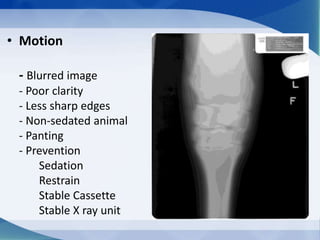

• Motion

- Blurred image

- Poor clarity

- Less sharp edges

- Non-sedated animal

- Panting

- Prevention

Sedation

Restrain

Stable Cassette

Stable X ray unit